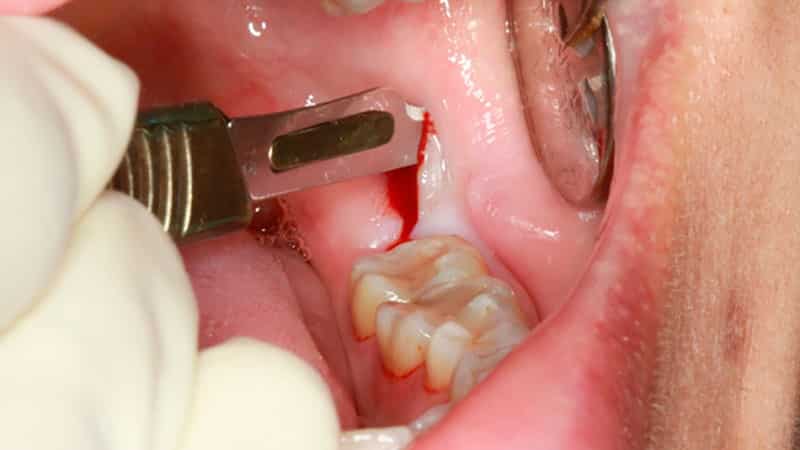

Удаление зубов мудрости – это сложная и специфическая процедура, в ходе которой хирург выполняет операцию с использованием специальных щипцов. Перед началом вмешательства пациенту вводят анестезию, после чего врач делает разрез на десне и высверливает небольшую лунку в костной ткани.

Если это необходимо, зуб может быть распилен на части с помощью стоматологического диска или бор. Затем в альвеолярное отверстие помещается лекарственное средство, и рана зашивается. Эта операция считается максимально безопасной, так как она снижает риск травмирования слизистой оболочки, соседних зубов и костных тканей.

При сложном удалении зубов мудрости хирург применяет бормашину, выполняет разрезы и сшивает раны. Обычно такая операция требуется для ретинированных или горизонтально расположенных зубов. Врачам часто необходимо удалить часть кости, чтобы получить доступ к зубу и его корням.

Процедура проводится с использованием мощных обезболивающих в условиях хирургического кабинета. Все необходимые антисептические меры обеспечивают стерильность помещения. Через три дня после операции рану зашивают рассасывающимися нитями, которые удаляются только после полного заживления.